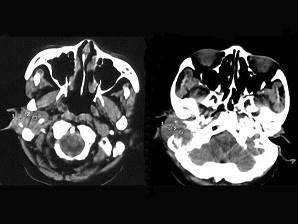

女,56岁,右侧中耳术后发现右外耳道新生物一年,PE:右外耳道内段被新生物充满,CT如图所示,应诊断为 ( )A、听神经瘤B、中耳结核...